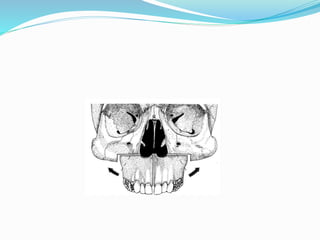

 Subcranial L F 3 osteotomy

1. Zygomatic osteotomy

2. Frontozygomatic sutures – 1cm

3. Orbital floor

4. Nazofrontal suture

5. Intraoral incision

6. Intraoral disection

7. Ptrygoid osteotomy

8. Vomer osteotomy

9. Disimpaction by forceps

10. LF 1 osteotomy if needed

11. Resuspention and forced duction test